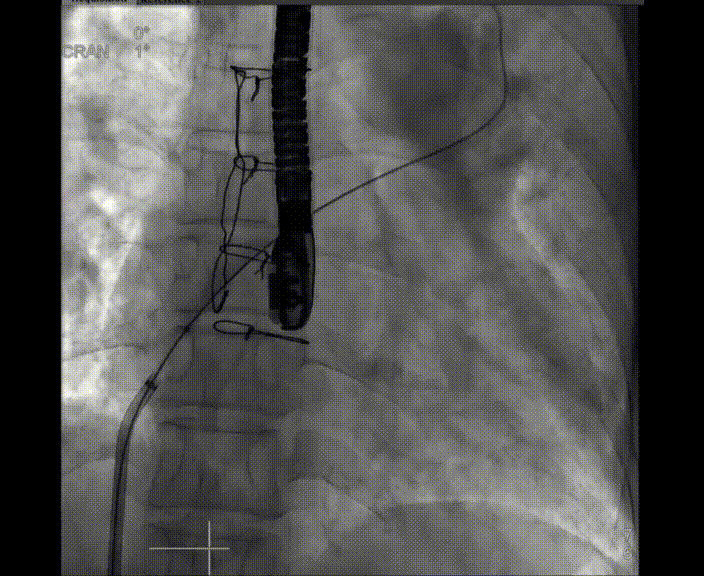

術中首先在局麻下穿刺股動脈、股靜脈,完成心導管檢查評估后轉為全麻,在食道超聲引導下穿刺房間隔,穿刺成功后將加硬導絲送入左上肺靜脈建立軌道,根據(jù)患者病情行球囊預擴張后植入6mm孔徑房間隔造孔支架,經(jīng)透視及食道超聲評估支架左右盤展開良好,夾持于房間隔兩側,固定穩(wěn)定、位置良好,食道彩超顯示房水平右向左為主分流,分流孔直徑符合預期大小,心導管檢查評估達到預期效果,釋放造孔支架。術后12h患者下床活動,恢復順利,擬于近日完善術后評估后出院。